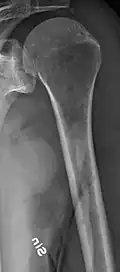

The diagnostic examination of a person with suspected multiple myeloma typically includes a skeletal survey. This is a series of X-rays of the skull, axial skeleton, and proximal long bones. Myeloma activity sometimes appears as "lytic lesions" (with local disappearance of normal bone due to resorption) or as "punched-out lesions" on the skull X-ray ("raindrop skull"). Lesions may also be sclerotic, which is seen as radiodense.[76] Overall, the radiodensity of myeloma is between −30 and 120 Hounsfield units (HU).[77] Magnetic resonance imaging is more sensitive than simple X-rays in the detection of lytic lesions. An MRI may supersede a skeletal survey, especially when vertebral disease is suspected. Occasionally, a CT scan is performed to measure the size of soft-tissue plasmacytomas. Nuclear Medicine Bone scans are typically not of any additional value in the workup of people with myeloma (no new bone formation; lytic lesions not well visualized on nuclear bone scan).

Multiple myeloma in the upper arm -

Humerus with multiple myeloma lesions -